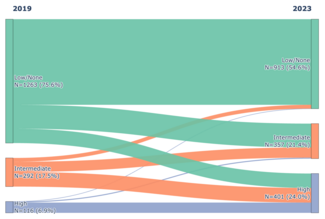

Therefore, we recommend following a staged procedural strategy for treatment of SVC thrombus (Diagram 1). When patients present with SVC thrombus, IPMT should be attempted first (Step 1), followed by balloon angioplasty (Step 2), and then stenting (Step 3), depending on the ultimate results. We define “good result” as less than 30% stenosis seen on the follow-up venogram with less than 5 mm Hg of pressure gradient along with restoration of the respiratory variation in the distal segment. If the repeat angiogram and pressure calculation reveal a good result at any step, the procedure can be aborted with adequate outpatient follow-up in 1 month.